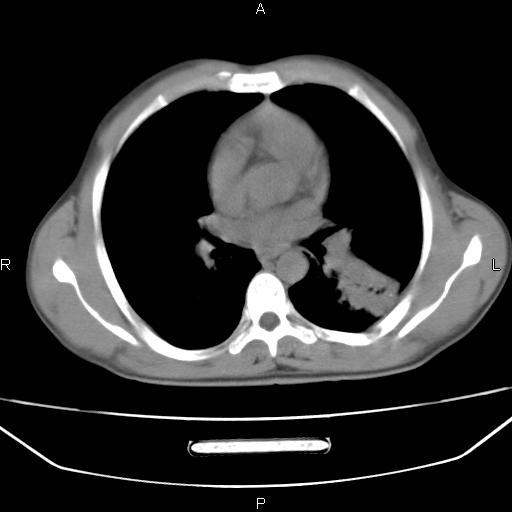

患者,男,40岁。间断发热,咳嗽二十余日。体温最高达38.9° 在当地诊所抗炎治疗三天后体温降至正常,患者自行停药。今又发热。胸片示,左下肺阴影。

左下肺片状高密度影,境界模糊,密度不均,考虑感染性病变可能性大,建议抗炎治疗后复查。左肺门增大,不除外占位性病变,必要时支气管镜检。